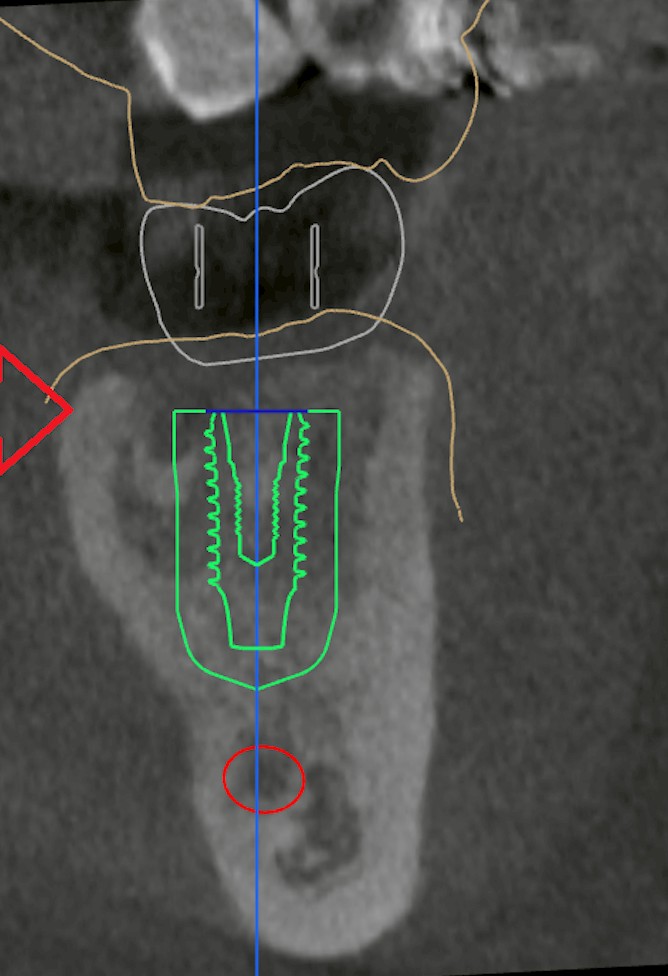

◆まとめ:最適なタイミングは“CTで決める”のが正確

インプラント治療は、

「抜歯後◯ヶ月」と一律に決めるものではなく、

CT画像で骨の再生状態を確認しながら最適な時期を判断します。

当院では、

無理のない計画を立てるために、

抜歯後の経過観察とCTによる定期チェックを行い、

最も治りやすいタイミングを一緒にデザインしていきます。